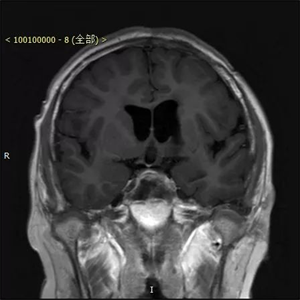

患者术前资料(下图)